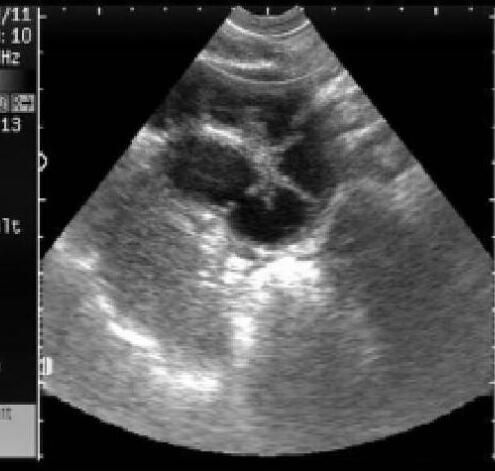

犬子宫蓄脓的典型B超声像图为:

犬子宫积脓指子宫腔内积有脓液,是发情后期的一种疾病,特征是子宫内膜异常并继发细菌感染。子宫内蓄积大量脓性渗出物不能排出时,称为子宫蓄脓。

早期患子宫内膜炎B超诊断很困难,随着子宫增粗,子宫内膜炎容易诊断,等患病到一定程度化脓炎症的脓汁增多,更容易用超声诊断。